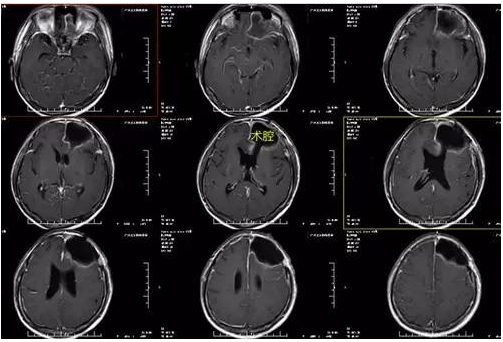

黄某某,男,47岁,头痛1周入院,入院后予完善相关检查,术前磁共振显示额叶病变最大直径5公分,肿瘤囊性变,左侧额叶多发囊状异常信号影,右侧半卵圆中心异常信号影。完善术前准备后,手术由神经外一科主任张良主刀完成,行全麻下左侧额叶胶质瘤+鞍区脑膜瘤切除术,术程顺利,术后复查头颅CT及MR提示术后改变,肿瘤全切除,术后病理提示间变性少突胶质细胞瘤(WHO III级),鞍区病变提示过渡型脑膜瘤(WHO I级)。

↓术后复查